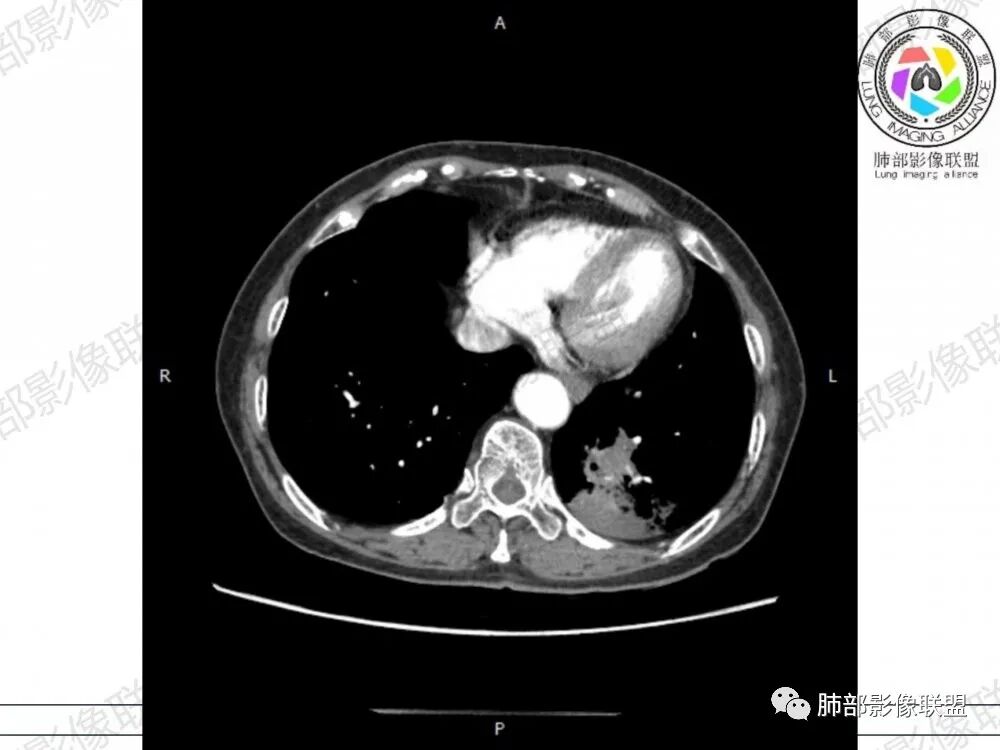

内部没结构

应该是空洞

这是啥?

如果是支气管,说明局部有占位效应,将支气管推移

2、影像表现:无肺气肿背景,病变定位于左肺下叶背内侧基底段,病灶呈不规则团块影,靠近胸膜侧,其内密度不均匀,内见空洞、实变及磨玻璃影,磨玻璃影呈碎石路征,边界清楚,实性肿块边界膨隆,其内见空洞。空洞周围比较实。病灶较大的支气管通畅,细小的支气管成“枯枝征”。无胸膜增厚及胸膜腔积液,增强扫描呈中度强化,见血管造影征。

1、粘液型腺癌仅占肺原发腺癌的3%左右,粘液多,易气道播散,支气管破坏不明显,不仅是大的支气管,小的支气管大多也没破坏,较大的支气管通畅,细小的支气管充满粘液,从而形成“枯枝征”,本病例病灶内可见枯枝征,是诊断粘液腺癌特点之一。

2、典型的粘液腺癌,收缩力很弱,肺泡壁断裂常有,张力存在,早期较少出现张力表现,破坏力偏弱,支气管与肺血管大多保留,所以增强病灶内见强化血管影(血池),也是粘液腺癌另一个特点。